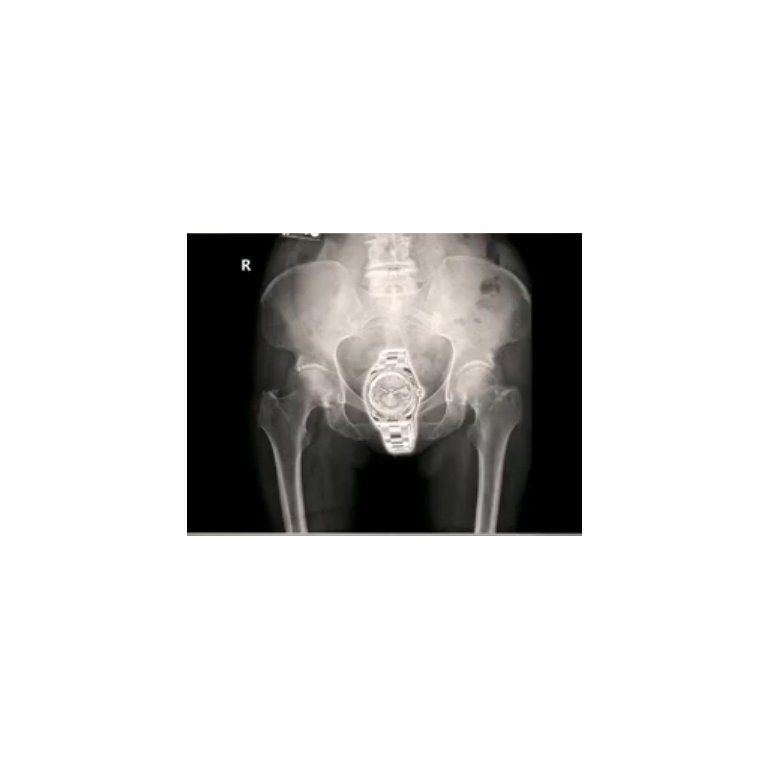

Las autoridades registraron a la mujer y decidieron hacerle unas radiografías y en ese momento descubrieron que el Rolex se encontraba escondido en su vagina.

Rolex en la vagina.jpg